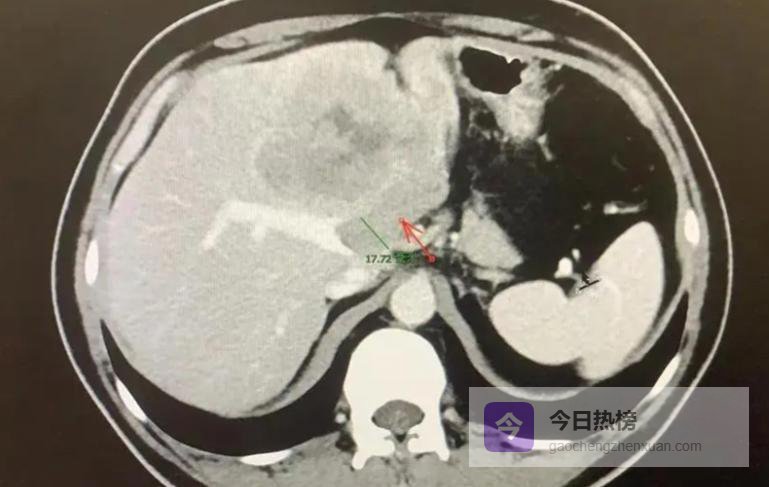

在动物试验中,汤院士观察到患有肝癌的老鼠经过科学训练后坚持游泳,其存活期比未进行运动的老鼠延长了大约17%(70天对比60天),但过度锻炼反而使存活时间缩短至50天。